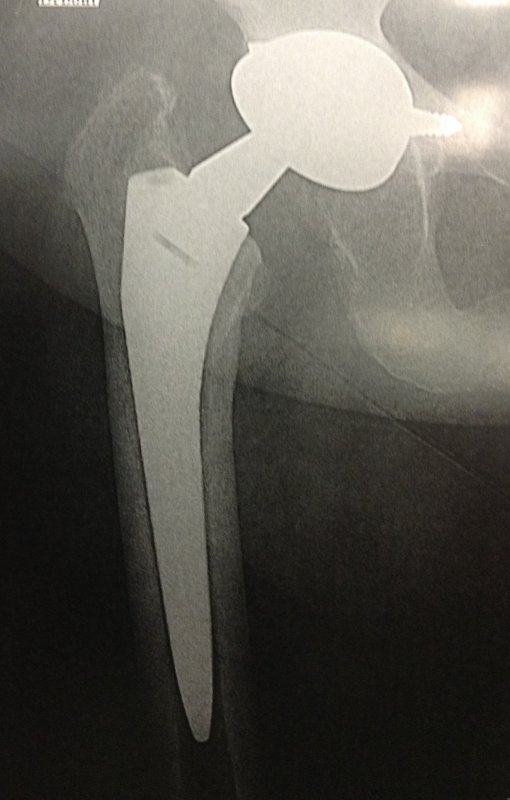

Il existe actuellement sur le marché un grand nombre deprothèses de formes et de tailles différentes, mais elles sont toutes constituées de deux implants indépendants l’un de l’autre : une pièce fémorale et une cupulecotyloïdienne.

Le cotyle prothétique s’implante dans le bassin à l’endroit du cotylenaturel. Il est composé d’une cupule hémisphérique en polyéthylène, métal ou céramique, qui constitue la surface de glissement de l’articulation prothétique. Dans la plupart des modèles, cette surface de glissement est insérée dans une cupule métallique assurant le contact avec l’os du bassin.

La pièce fémorale est composée d’une tête fémorale métallique ou céramique sphérique, enchâssée sur la tige fémorale. Le diamètre de la tête prothétique est identique au diamètre interne de la cupule cotyloïdienne. Elle assure la congruence et la stabilité de l’articulation artificielle, et autorise des mouvements d’une amplitude très semblable à celle de la hanche normale. La tige d’implantation fémorale sert à ancrer la prothèse dans le fût fémoral osseux.

Cotyle titane press fit Insert en céramique Tige titane Tête fémorale céramique ou double mobilité